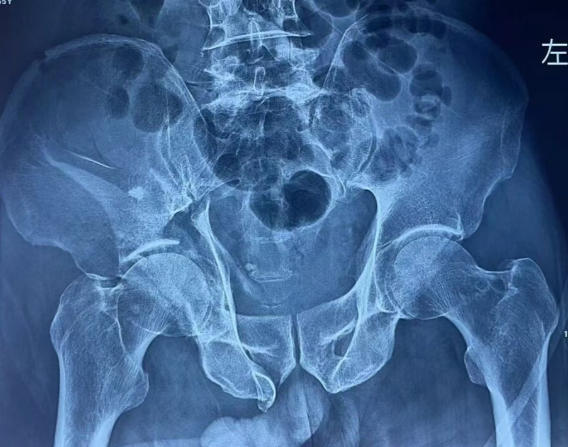

术前

一场高处坠落,让65岁的老人生命垂危:骨盆多发粉碎性骨折、髋臼中心性脱位、尺骨鹰嘴骨折,同时合并心律失常、肺挫伤、贫血与感染……伤情复杂、基础病多,救治难度极大。